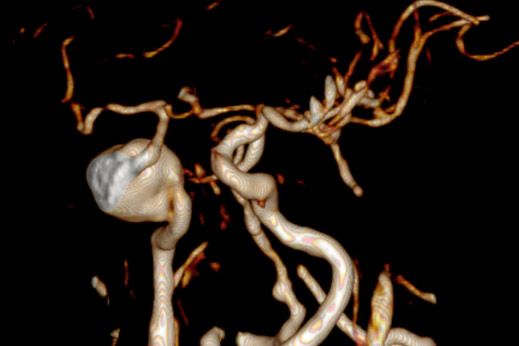

Die Magnetresonanztomographie nutzt keine Röntgenstrahlen sondern Magnetfelder und hochfrequente elektromagnetische Wellen. Das durch hochempfindliche Antennen gewonnene Signal wird in einem komplizierten Auslese- und Messverfahren umgesetzt und in ein Bild umgewandelt.

Der Vorteil der MRT ist die oft bessere Darstellbarkeit entzündlicher und tumoröser Veränderungen in sämtlichen Weichteil-Geweben, bzw. -Strukturen; Nerven- und Hirngewebe werden z.T. erst durch die MRT-Untersuchung hinreichend beurteilbar. Oft wird Kontrastmittel zusätzlich benötigt, um Entzündungsherde oder auch Tumorgewebe noch besser darzustellen.

• Gefäße